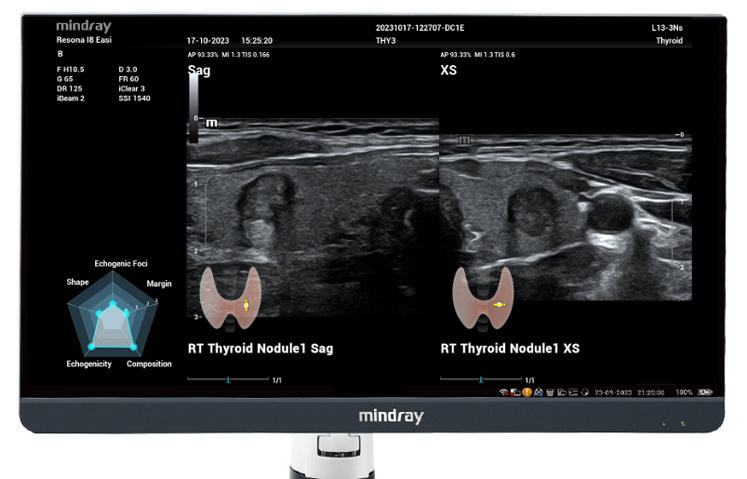

Für die Ultraschalltechnologie stellt die ZST+-Plattform einen bedeutenden Fortschritt dar, da sie statt der herkömmlichen Strahlformung die Kanaldatenverarbeitung verwendet. Diese bahnbrechende Innovation löst übliche Zielkonflikte zwischen räumlicher Auflösung, zeitlicher Auflösung und Homogenität des Gewebes auf, woraus sich eine beispiellose Bildqualität ergibt, die den Weg frei macht für unendlich viele Bildgebungslösungen.

Das Resona I8 weist vielfältige klinische Lösungen auf, die speziell für den jeweiligen Anwendungsbereich entwickelt wurden. Die Technologie baut auf einem tiefgreifenden Verständnis verschiedener klinischer Szenarien auf und bietet eine umfassende Serie fortschrittlicher Diagnoseinstrumente, beispiellose Intelligenz und präzise Analysen zur Verbesserung von Diagnosesicherheit, Qualitätskontrolle und Scaneffizienz.